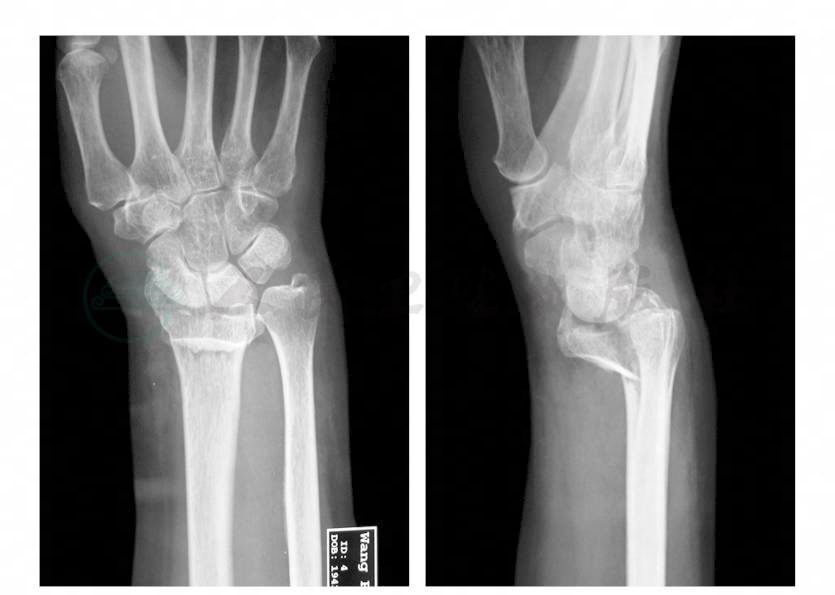

患者,女性,61岁。患者入院前5小时骑自行车时摔倒,右手掌撑地,伤及右腕部,即感右腕部疼痛,活动障碍,伴肿胀,右手桡侧三指麻木。就诊于北京大学人民医院急诊,行X线检查提示为“右桡骨远端骨折,桡骨远段小骨折块向掌侧移位,尺骨茎突骨折”。遂入院进一步治疗。既往高血压病史10余年,口服药物治疗,血压控制在130/80mmHg。12年前行右卵巢囊肿切除术。10年前因子宫肌瘤行子宫全切术。8年前行甲状腺腺瘤切除术。查体:右腕部明显肿胀,压痛明显,可触及骨擦感,腕关节活动障碍。血运正常。右手桡侧3个半手指感觉麻木。辅助检查:X线片(急诊):右桡骨远端骨折,桡骨远段小骨折块向掌侧移位,尺骨茎突骨折(图1)。

图1 术前腕关节正侧位X线片